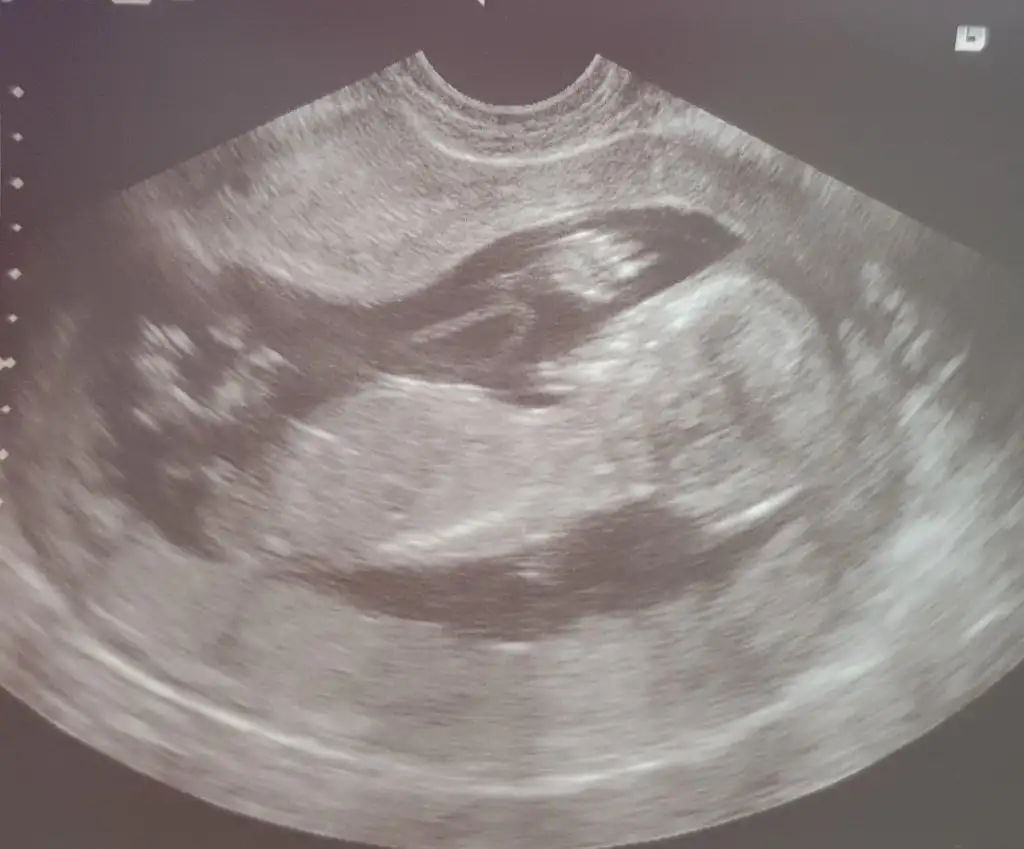

Bu haftalarda iki organ da birbirine cok benziyor 15 haftadan sonra daha net olur dedi. Ama ozamana kadar da nifty testi sonucu cikacak. Ben ne anladim bu isten 🤣

Evet oyleymis. Ya saglikli olsunlar da cinsiyet 2. Planda. Ama insan yine de merak ediyor. 😁

Allah saglikla kucagimiza almayi nasip eder insallah 😊